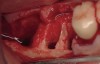

The patient was a 71-year-old man with significant caries and subsequent bone loss associated with tooth No. 30. The septal bone was lost, with the exception of the coronal aspect, resulting in a "bridge of bone" connecting the buccal and lingual cortices of the site (Figure 1). After reflection of the full-thickness buccal and lingual flaps, extraction, and manual and ultrasonic debridement of the socket to remove all visible soft-tissue remnants, the defect was obturated with the rhBMP-2/ACS material (Figure 2).

Figure 2  Obturation of extraction socket with rhBMP-2/ACS.

Figure 2